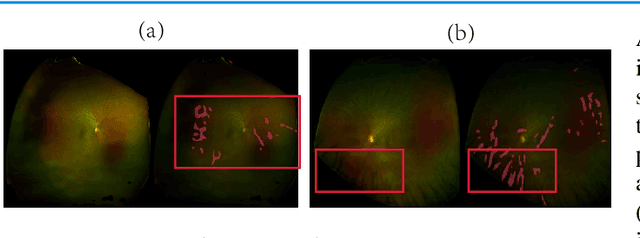

Recently, ultra-widefield (UWF) 200-degree fundus imaging by Optos cameras has gradually been introduced because of its broader insights for detecting more information on the fundus than regular 30-degree - 60-degree fundus cameras. Compared with UWF fundus images, regular fundus images contain a large amount of high-quality and well-annotated data. Due to the domain gap, models trained by regular fundus images to recognize UWF fundus images perform poorly. Hence, given that annotating medical data is labor intensive and time consuming, in this paper, we explore how to leverage regular fundus images to improve the limited UWF fundus data and annotations for more efficient training. We propose the use of a modified cycle generative adversarial network (CycleGAN) model to bridge the gap between regular and UWF fundus and generate additional UWF fundus images for training. A consistency regularization term is proposed in the loss of the GAN to improve and regulate the quality of the generated data. Our method does not require that images from the two domains be paired or even that the semantic labels be the same, which provides great convenience for data collection. Furthermore, we show that our method is robust to noise and errors introduced by the generated unlabeled data with the pseudo-labeling technique. We evaluated the effectiveness of our methods on several common fundus diseases and tasks, such as diabetic retinopathy (DR) classification, lesion detection and tessellated fundus segmentation. The experimental results demonstrate that our proposed method simultaneously achieves superior generalizability of the learned representations and performance improvements in multiple tasks.